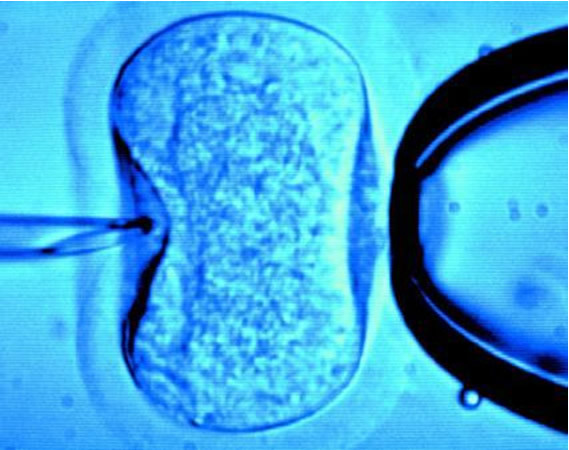

ICSI

Intra- cytoplasmic sperm injection (ICSI) is a technique for the treatment of extreme male infertility in which sperm are injected directly into the body (cytoplasm) of the egg. It is especially useful for patients where the male partner has a very low sperm count (oligozoospermia), poor sperm motility (asthenozoospermia) or too many abnormal sperms (teratozoospermia).

In ICSI all the steps are similar to the procedure of IVF, except the step of fertilization. Normally in IVF one egg is mixed with 100,000 sperms and one of the sperms fertilizes the egg on its own. In contrast, in ICSI each egg is held and injected with a single live sperm. This micro-fertilization is done with the help of a machine called the Micromanipulator.